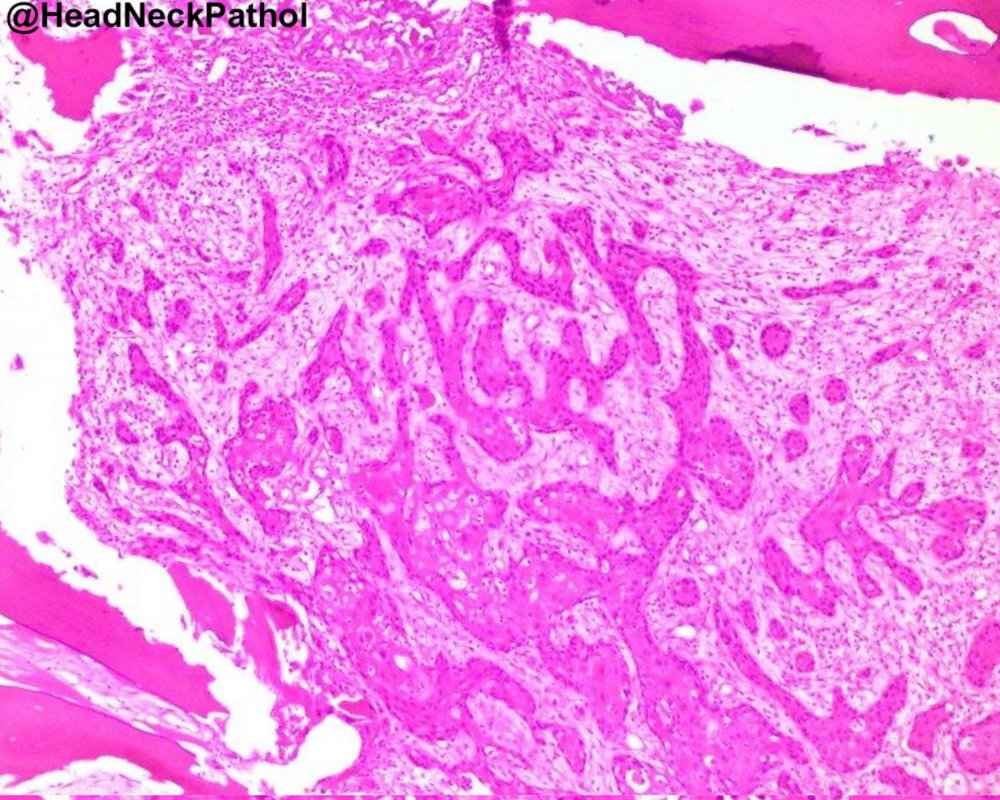

Characterization of CD8 + & CD68 + Microenvironment & PDL1 Expression in HPV-related Multiphenotypic Sinonasal Carcinoma